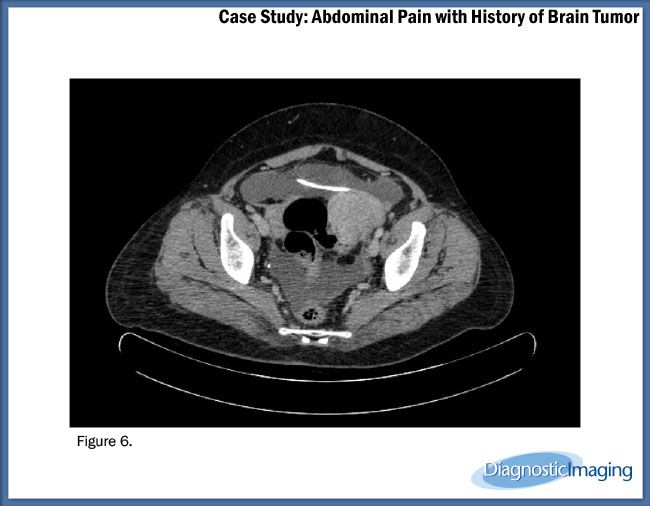

Case History: A 45-year-old patient with history of brain tumor with ventriculoperitoneal shunt presented with complaints of abdominal pain.